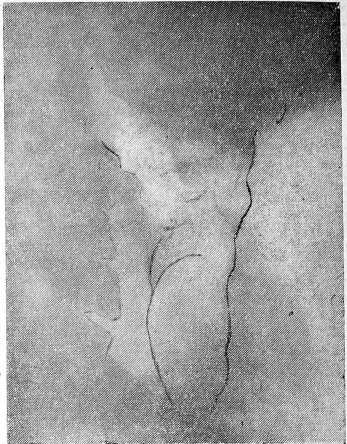

Убедительными рентгенологическими симптомами опухоли щитовидной железы являются смещения и деформация трахеи. Деформация трахеи, характер ее контуров, ширина просвета могут быть определены на боковых рентгенограммах шеи. Иллюстрацией является приводимое ниже наблюдение.

Ц., 43 лет. Год назад заметила увеличение щитовидной железы. В течение месяца беспокоит одышка, охриплость голоса.

Щитовидная железа увеличена. В нижнем полюсе левой доли и в области перешейка пальпируются единичные плотные узлы. Регионарные лимфатические узлы не увеличены. При рентгенологическом исследовании органов грудной клетки в легких и средостении патологии не выявлено. При обследовании ЛОР-органов установлено выпячивание в просвет трахеи ее передней стенки. На обзорных рентгенограммах области шеи отмечается увеличение тени щитовидной железы, она неоднородна, содержит кальцинаты в виде неправильных линейных фигур. На боковой рентгенограмме шеи (рис. 1) на уровне С6_7—Д1 видна увеличенная тень щитовидной железы с участками обызвествления. Щитовидная железа сдавливает переднюю стенку трахеи. Внутренний контур трахеи неровный, бугристый. Ретротрахеальное пространство не изменено.

Произведена левосторонняя гемитиреоидэктомия, удалена опухоль перешейка. Гистологический диагноз: злокачественная аденома.

На уровне С6-7 и Д1 увеличенная щитовидная железа с участками кальцификатов сдавливает трахею по передней стенке. Внутренний контур трахеи здесь неровный, бугристый. Ретротрахеальное пространство не изменено.

Рис. 1. Рентгенограмма шеи в боковой проекции больной Ц., 43 лет.

На уровне C6-7 и Д1 увеличенная щитовидная железа с участками кальцификатов сдавливает трахею по передней стенке. Внутренний контур трахеи здесь неровный, бугристый. Ретротрахеальное пространство не изменено.